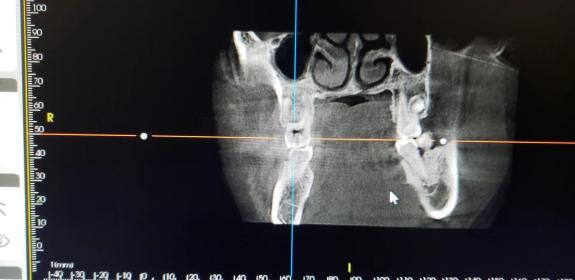

CBCT显示,右上六冠根折裂至髓室底

CBCT显示右上六冠根折裂至髓室底